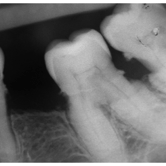

Fractura Radicular Vertical

Una fractura radicular vertical es una fisura que se extiende a lo largo de la raíz del diente, a menudo causada por un trauma o una presión excesiva.

Los pacientes suelen sentir dolor al morder y pueden notar hinchazón.

La fractura generalmente requiere la extracción del diente, ya que es difícil de reparar. Es crucial tratarla rápidamente para evitar infecciones.